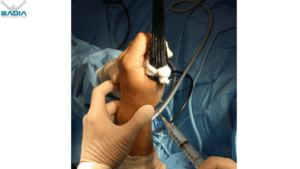

Basal Joint Arthritis Thumb arthritis is the most common form…